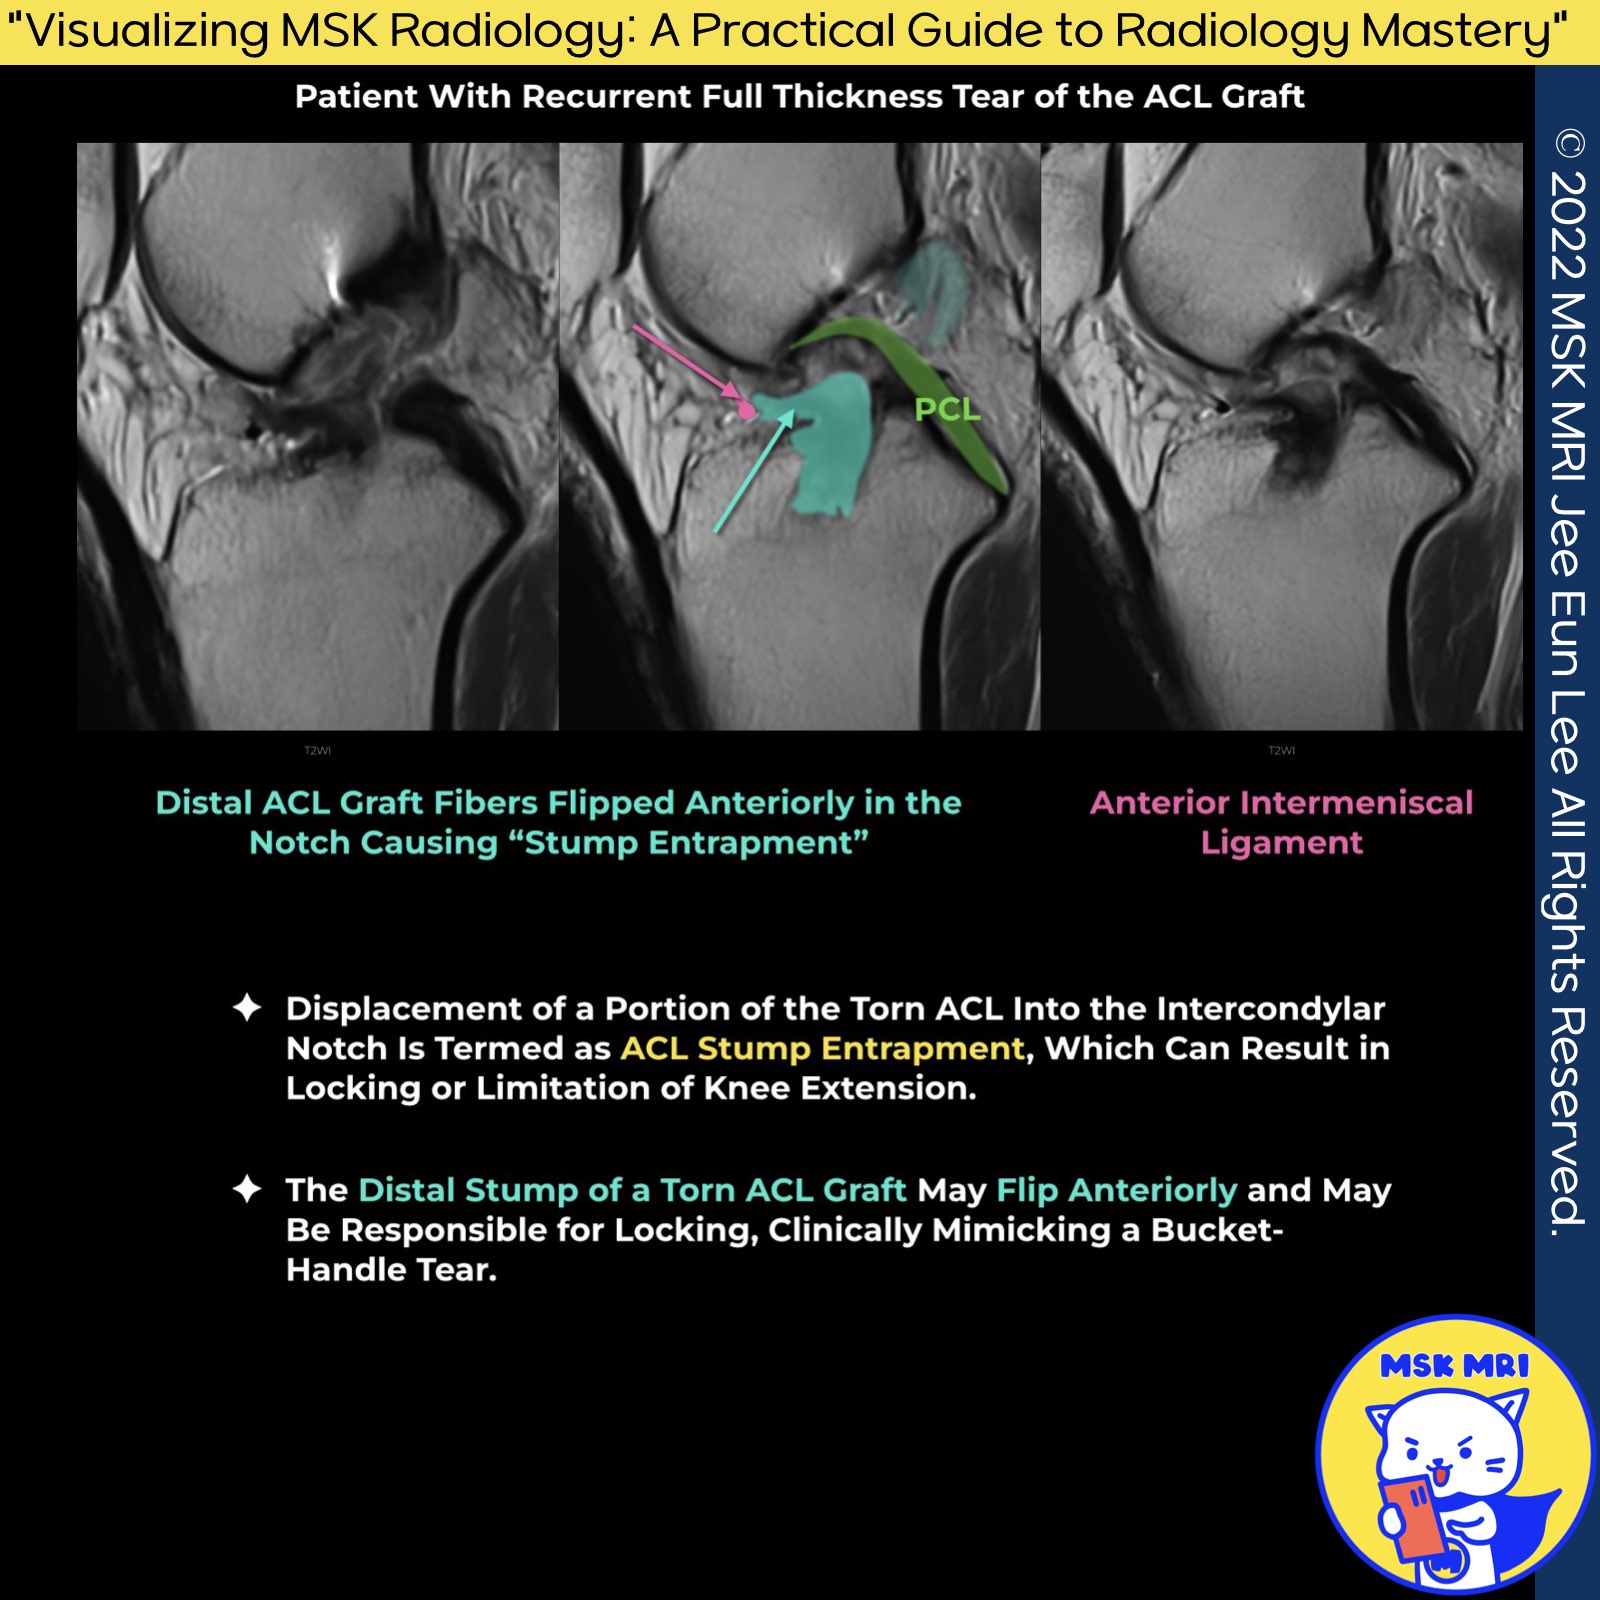

- Description: Occasionally, partially torn graft fibers are displaced into the intercondylar notch, mimicking a cyclops lesion. This phenomenon is known as a "pseudo-cyclops lesion."

- Distinguishing Features: Unlike a true cyclops lesion, a pseudo-cyclops lesion involves a portion of the fibers extending into the tibial or femoral tunnels

- Characteristics: Type 2 SE lesions are characterized by a tongue-like free end and angulation of the ACL stump.

- Appearance: Unlike the type 1 lesion, which has a mass-like appearance, the type 2 SE lesion shows the anterior portion of the torn ACL folded upon itself. This results in a thin, tongue-like free end extending anteriorly out of the intercondylar notch.